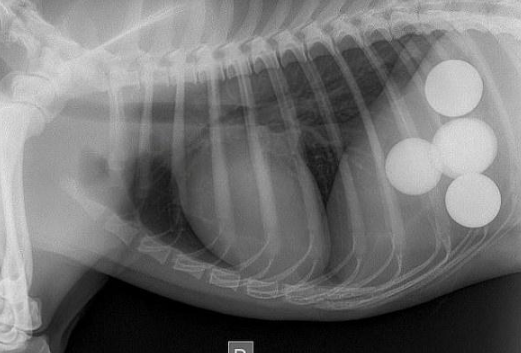

可是半天的時间过去,狗狗的腹部還是沒有消散,主人这才意识到,狗子应该是误吞了哪些东西进来,导致本身没法消化,因此将狗狗抱去医院体检,結果发觉了好多个环形的东西在肚里,但大夫在短期内内也没法鉴别是什么东西。

之后历经大夫长达2个多钟头的勤奋,总算将狗狗身体的环形物件排了出去,原先狗狗是误吞了五个高尔夫,导致没法消化,而高尔夫一般 全是由硬硫化橡胶或是塑胶等材料构成,更何况狗子也是全部吞进去的,因而消化不上也是一切正常的。